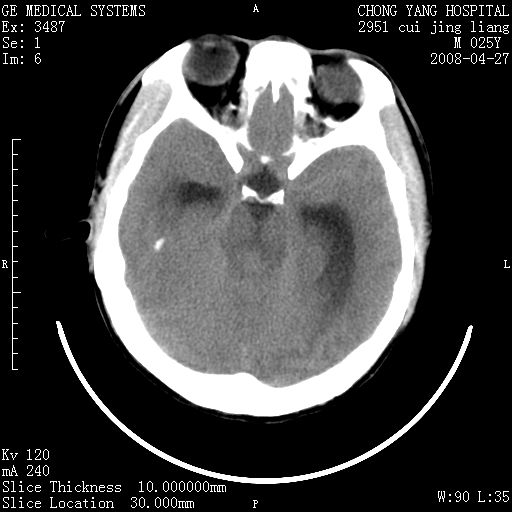

以下是引用余辉在2008-4-27 17:08:00的发言:[br]支持考虑松果体区畸胎瘤伴梗阻性脑积水,左侧室前角还有脂液滴?

以下是引用王仕学在2008-4-27 16:25:00的发言:[br]软组织肿块+脂肪球,考虑松果体区畸胎瘤可能性大。

以下是引用随光逐影在2008-4-27 20:13:00的发言:[br]1)考虑为:第三脑室后部、松果体区畸胎瘤。2)脑积水(梗阻性)。

以下是引用jinguoji在2008-4-27 23:41:00的发言:[br]考虑松果体区肿瘤引起梗阻性脑积水。